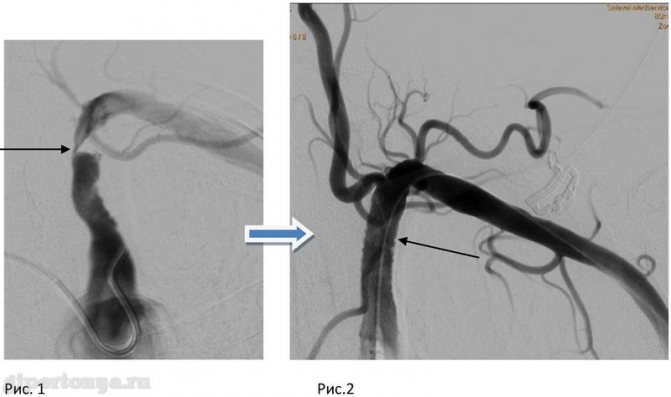

- Когда уровень кровяного давления на руке значительно меньше, чем на нижней конечности, то это может свидетельствовать о проблемном кровоснабжении верхней конечности. Такая аномалия может быть вызвана, например синдромом подключичного обкрадывания, который возникает в результате образования атеросклеротической бляшки.

Это зависит от размера используемой манжеты, а также от того, измерялось ли давление прямым (с использованием внутриартериального катетера) или непрямым (основанном на выслушивании тонов Короткова) методом. Если используется бедренная манжета нужного размера, то измеренное в подколенной ямке систолическое давление может или равняться зарегистрированному на руке, или быть выше его.

В последнем случае разница между величинами давления может достигать 20 мм рт. ст. Если систолическое давление на ногах ниже, чем на руках, то следует заподозрить обструктивное поражение аорты ниже места отхождения подключичных артерий или же стенозирование магистральных артерий нижних конечностей [76J.